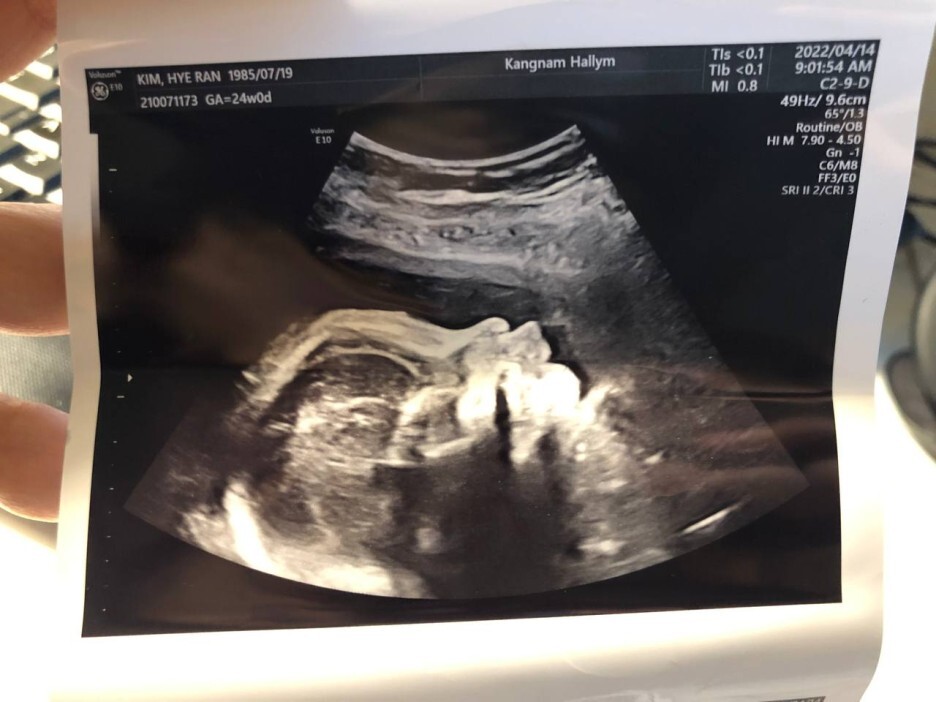

4월 14일 목요일(24주차 0일)

BPD(Biparietal Diameter, 위에서 볼 때 태아 머리 단면의 가장 긴 길이): 5.59cm

HC(Head Circumference, 태아 머리둘레): 21.64cm

AC(Abdominal Circumference, 배 둘레): 19.99cm

EDD(Expected Date of Delivery, 출산 예정일): 2022년 8월 4일

FL(Femur Length, 허벅지뼈 길이): 4.32cm

GA(Gestational Age, 임신 주차): 24주차 1일

EFW(Estimated Fatal Weight, 태아 예상 체중)=EBW(Estimated Body Weight): 680g

FHR(Fetal Heart Rate, 심장박동 수): 155bpm

CL(Cervical Length, 자궁경부 길이): 3.77cm

AF(Amniotic Fluid, 양수): 정상